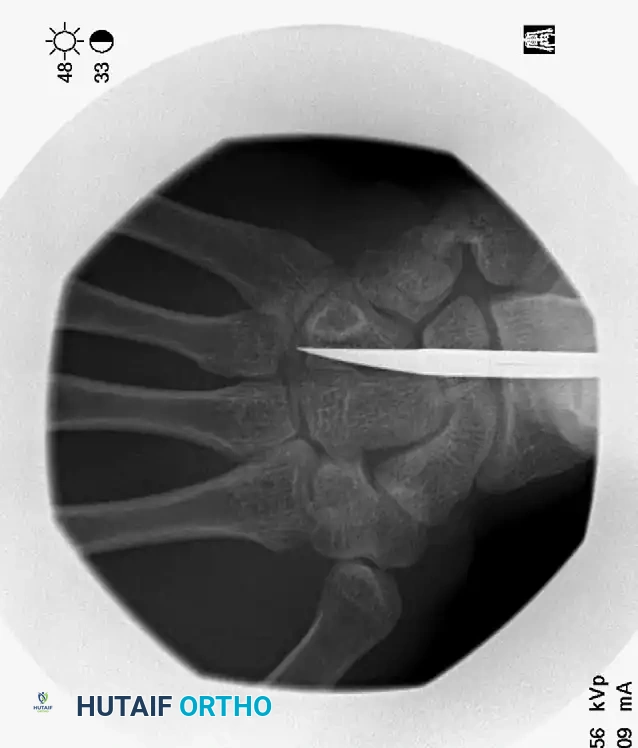

FIGURE 67-38C: Fluoroscopic view demonstrating the correct entry position and trajectory of the intramedullary wire.

Mount the unbent proximal end of the K-wire into a T-handle chuck (manual insertion provides superior tactile feedback compared to power driving). Advance the wire down the canal until it reaches the fracture site. Confirm the reduction fluoroscopically, then pass the wire across the fracture into the distal fragment.

Use live fluoroscopy to ensure intramedullary containment of the wire, especially as it crosses the fracture site. The blunt, curved tip should be advanced until it sits securely in the dense subchondral bone of the metacarpal head, stopping just short of the articular cartilage.